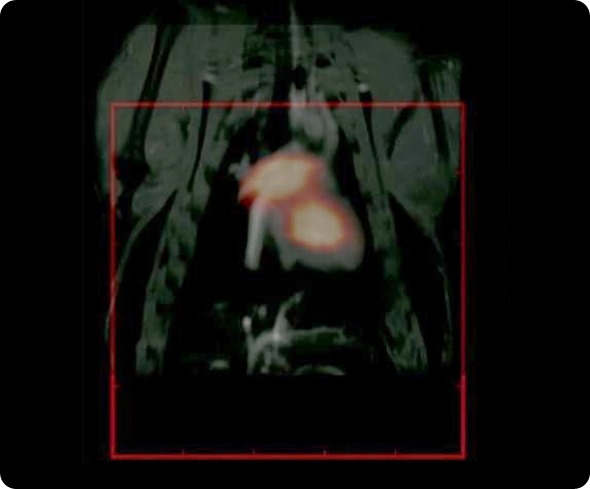

With Steve, we have performed some fantastic imaging that is of relevance to cardiovascular imaging. We have worked with rat models. His imaging technique takes much longer to image; it takes about 10 minutes to get a good image, but because our particles circulate for long enough, we have been able to resolve the jugular vein and various other vasculature in the head of rodent models. It is really very spectacular work that we have done with Steve.

For example, we have been working with a mouse cancer model of a brain tumor, which is a xenograft model, where the MPI tracer has been functionalized with a near-infrared fluorescent tag. We can inject them and see that it goes into the tumor, which we can image with the fluorescent tag. Where the potential of MPI comes in, is that we can resect these tumors and then take them to the MPS (magnetic particle spectrometer) and measure the signal from these tracers.

That’s the true advantage of MPI: the signal can be quantified in terms of the number of particles that are going into the tumor and how successful our targeting is. We use that kind of combination. Similarly, we combine our tracers with a radionuclide and then use existing modalities such as CT, PET to look at biodistribution. This is very important because, ultimately, what we are really interested in once you put the tracer in the body, is where it is going. Once we know that, the next question is really the long term biological fate of the particles. That is a really open question at this time.